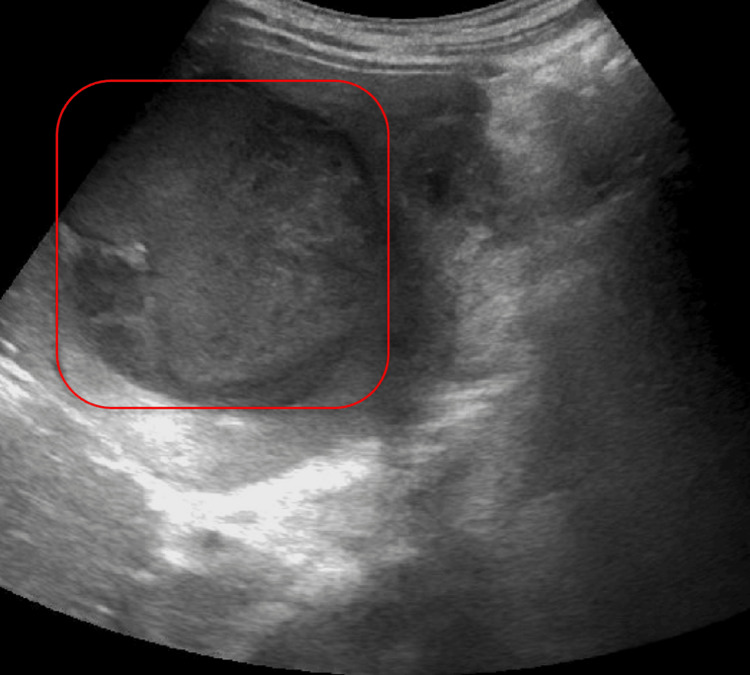

Post-procedure, the patient developed improved jaundice and abdominal pain and was able to tolerate a regular diet with discharge home on the fifth post-procedure day. He re-presented three weeks later due to progressive cramping abdominal right upper quadrant (RUQ) pain, nausea, and bilious emesis. An abdominal ultrasound and CT demonstrated a large 8.5 cm liver abscess in the right hepatic lobe, with a posterior defect in the hepatic margin of the gallbladder wall (Figures 4–6). There was noted septic thrombosis of the right portal venous system. He underwent emergent CT-guided percutaneous transhepatic drainage of the liver abscess, with cultures demonstrating Streptococcus anginosus. He was initiated on empiric IV piperacillin-tazobactam, followed by a transition to a four-week course of oral amoxicillin-clavulanate 875-125 mg twice daily after sensitivity results were completed. He was initiated on therapeutic enoxaparin followed by conversion to oral apixaban for a planned six-month course for portal thrombosis. Repeat CT imaging demonstrated stable portal thrombus without extension or enlarging hepatic abscess. He was discharged home with planned interval endobiliary stent removal and delayed interval cholecystectomy. No complications or recurrent symptoms were observed during the patient’s follow-up after discharge.

Once the gallbladder ruptures, the potential for serious complications increases dramatically [ref. 14]. In this case, bile and bacteria leaked from the gallbladder into surrounding structures, forming a fistula between the gallbladder and the liver [ref. 13]. This direct communication allowed the spread of infection into the liver parenchyma, resulting in a large hepatic abscess [ref. 15]. Gallbladder ruptures are rare, but when they occur, they often lead to the development of liver abscesses, which are polymicrobial in nature [ref. 16]. Streptococcus anginosus, a frequent pathogen in biliary infections, was cultured from this patient’s abscess, consistent with the fistulous connection between the inflamed gallbladder and the liver [ref. 17,ref. 18]. Imaging, including ultrasound and CT, played a crucial role in diagnosing both the gallbladder rupture and the liver abscess, guiding the therapeutic approach [ref. 19].